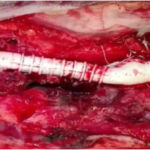

Ανεύρυσμα κοιλιακής αορτής-Ανοιχτή Αποκατάσταση

Η ανοιχτή αποκατάσταση ανευρύσματος κοιλιακής αορτής είναι χειρουργική επέμβαση κατά την οποία το παθολογικά διατεταμένο τμήμα της αορτής αντικαθίσταται με συνθετικό αγγειακό μόσχευμα για την αποκατάσταση της φυσιολογικής ροής του αίματος.